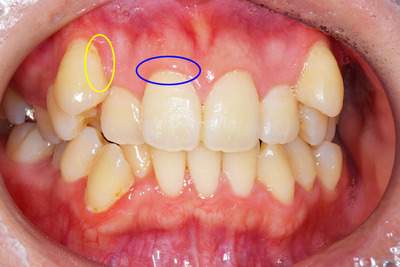

BEFORE

歯周病症例の治療前

黄色:歯の根本に黒い歯石が付着しているのがわかり

ます。

青色:歯にプラークが付着していると、歯の周りの歯ぐきに炎症があり、赤く腫れているのがわかり